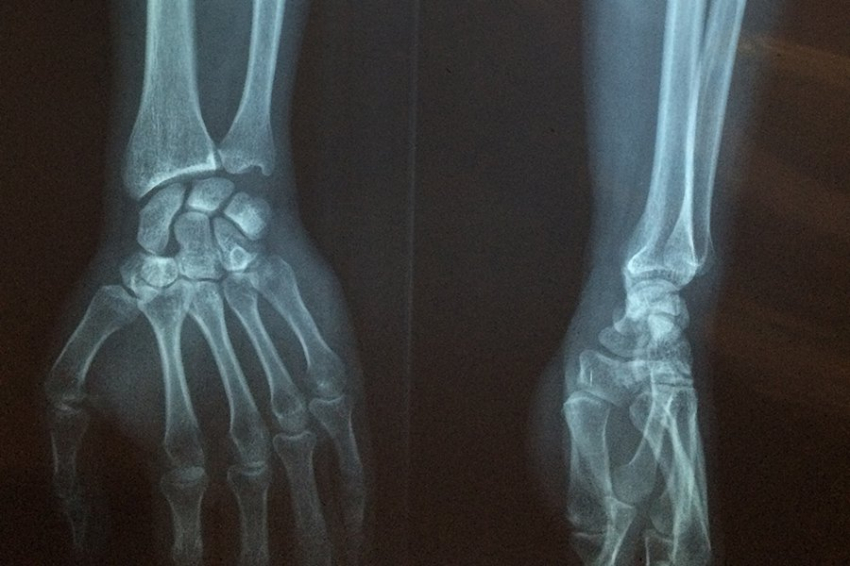

Чтобы человеческое тело не превратилось в аморфную массу, требуется 206-208 костей. Однако, каким бы крепким ни казался наш скелет, он постоянно меняется благодаря четко поставленному танцу клеток, которые его разрушают и восстанавливают. Теперь, направляя мощные рентгеновские лучи из ускорителя частиц на костные чешуйки древней окаменелости рыбы, исследовательская группа обнаружила, что такое перестроение костей, вероятно, началось по крайней мере 460 миллионов лет назад.

В современных скелетах крошечные кровеносные сосуды, которые проникают в твердый матрикс кости, обеспечивают проникновение клеток, называемых остеокластами, для разъедания старой кости и клеток, называемых остеобластами, для начала производства новой кости. Организацией процесса занимается третий набор клеток: остеоциты. Места восстановления, известные как остеоны, имеют характерные кольца, представляющие границы кровеносного сосуда и зоны существующей кости, разрушенной кости и новой кости. Процесс ремоделирования жизненно важен для восстановления и обновления кости, но у людей он может пойти не так, что приведет к остеопорозу, которым страдают более 10 миллионов человек только в Соединенных Штатах.